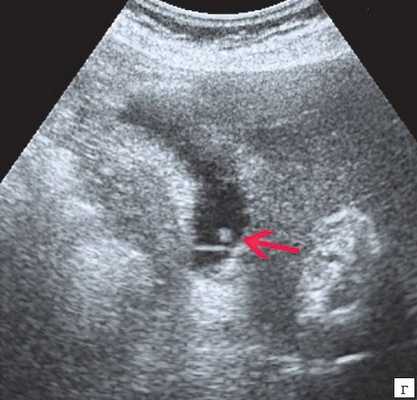

(Левый) На поперечном УЗ срезе правой доли печени определяется несколько эхогенных очагов В линейной формы, отбрасывающих «грязную» акустическую тень, что соответствует картине газа в желчных протоках.

(Правый) На поперечном УЗ срезе правой доли печени визуализируются несколько эхогенных очагов линейной формы, отбрасывающих «грязную» акустическую тень, что соответствует изменениям, возникающих при наличии газа в желчных протоках.